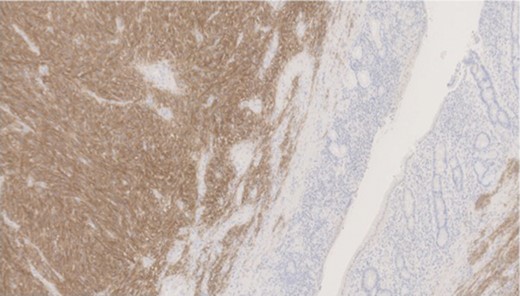

Pathology—GIST of spindle cell type (Figs 3 and 4), 90 mm in size, with complete local excision. Mitotic count—3 per 5 mm square. CD117 (Fig. 5) and DOG1 (Fig. 6) positive staining giving a prognostic group of moderate risk (Miettinen’s classification) of progressive disease. It is widely accepted that Interstitial Cells of Cajal (ICC) are pace maker cells of the gut and probable progenitor cells of GIST. Hyperplasia of ICC can be seen in cases with NF1, however, in this case this could not be shown in the background bowel (Fig. 7).

MNF staining the epithelium of the bowel while is negative in tumour cells.